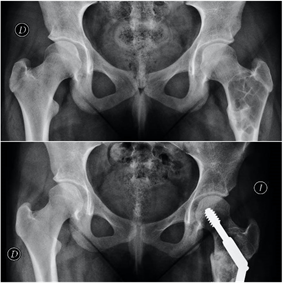

Metástasis en los huesos

En pacientes con historia previa de carcinoma, ante la presencia de dolor óseo debemos contemplar siempre la posibilidad de diseminación ósea metastásica. Las revisiones rutinarias de oncología suelen realizar rastreos periódicos a descartar posibles diseminaciones. En ocasiones la metástasis se descubre como una fractura, en ocasiones ante un traumatismo leve o incluso de forma espontánea. En otras ocasiones se detectan como microfracturas en los estudios oncológicos de gammagrafía o resonancia, tras un inicio insidioso de dolor en la zona.

El fémur es la localización principal, con predominio de la zona de la cadera. Otras localizaciones son la columna vertebral, la pelvis, los huesos planos y el húmero. En la espalda el dolor suele estar presente antes que los cambios radiográficos, mientras que cuando el dolor se localiza en los huesos largos suelen ya existir lesiones con riesgo de fractura.

En el cáncer diseminado el tratamiento de las metástasis suele ser paliativo, mediante estabilización de la fractura con osteosíntesis o implante de prótesis. En ocasiones la osteosíntesis se suplementa con aporte de cementos biológicos para aumentar la estabilidad o se realiza radioterapia complementaria. En casos de metástasis únicas, el tratamiento quirúrgico radical de la metástasis puede estar indicado, lo que hace necesaria la valoración conjunta de traumatología oncológica y oncología médica ante la detección de una lesión metastásica ósea en nuestra práctica.

Ante la sospecha de una fractura patológica de origen metastático debemos tener un enfoque multidiscilplinar, tanto traumatológico como oncológico, con fin de realizar tanto el tratamiento específico de la fractura como el estadiaje oncológico.